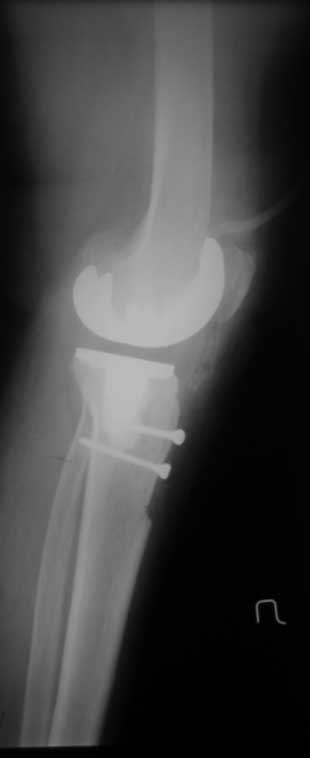

снимки

По данным R-грамм, хотя качество их не очень..., мне кажется имеется 2 основных ошибки: 1. высокий уровень остеотомии большеберцовой кости, при разгибетельных контрактурах его необходимо делать ниже.

2. Большой размер бедренного компонента. За счет этого переднезадний размер увеличен и ограничивает сгибание.

>1. высокий уровень остеотомии большеберцовой кости, при разгибетельных контрактурах его необходимо делать ниже.

уверяю вас, бедренный офсет не увеличен (снимок в ротации - ближайший п/о период, сложно вывести проекцию) экспериментируя с опилами к имеющимся проблемам можно было получить несбалансированное колено. Опил тибии стандартный на 10-ый вкладыш. Без рефиксированной бугристости колено было отлично сбалансировано, сгибание было до острого угла. проблема была именно в мягких тканях, конкретно в разгибательном аппарате, а не в опилах